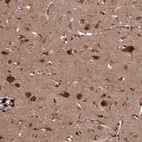

Immunohistochemical staining of human cerebral cortex shows strong cytoplasmic and nuclear positivity in neuronal cells.